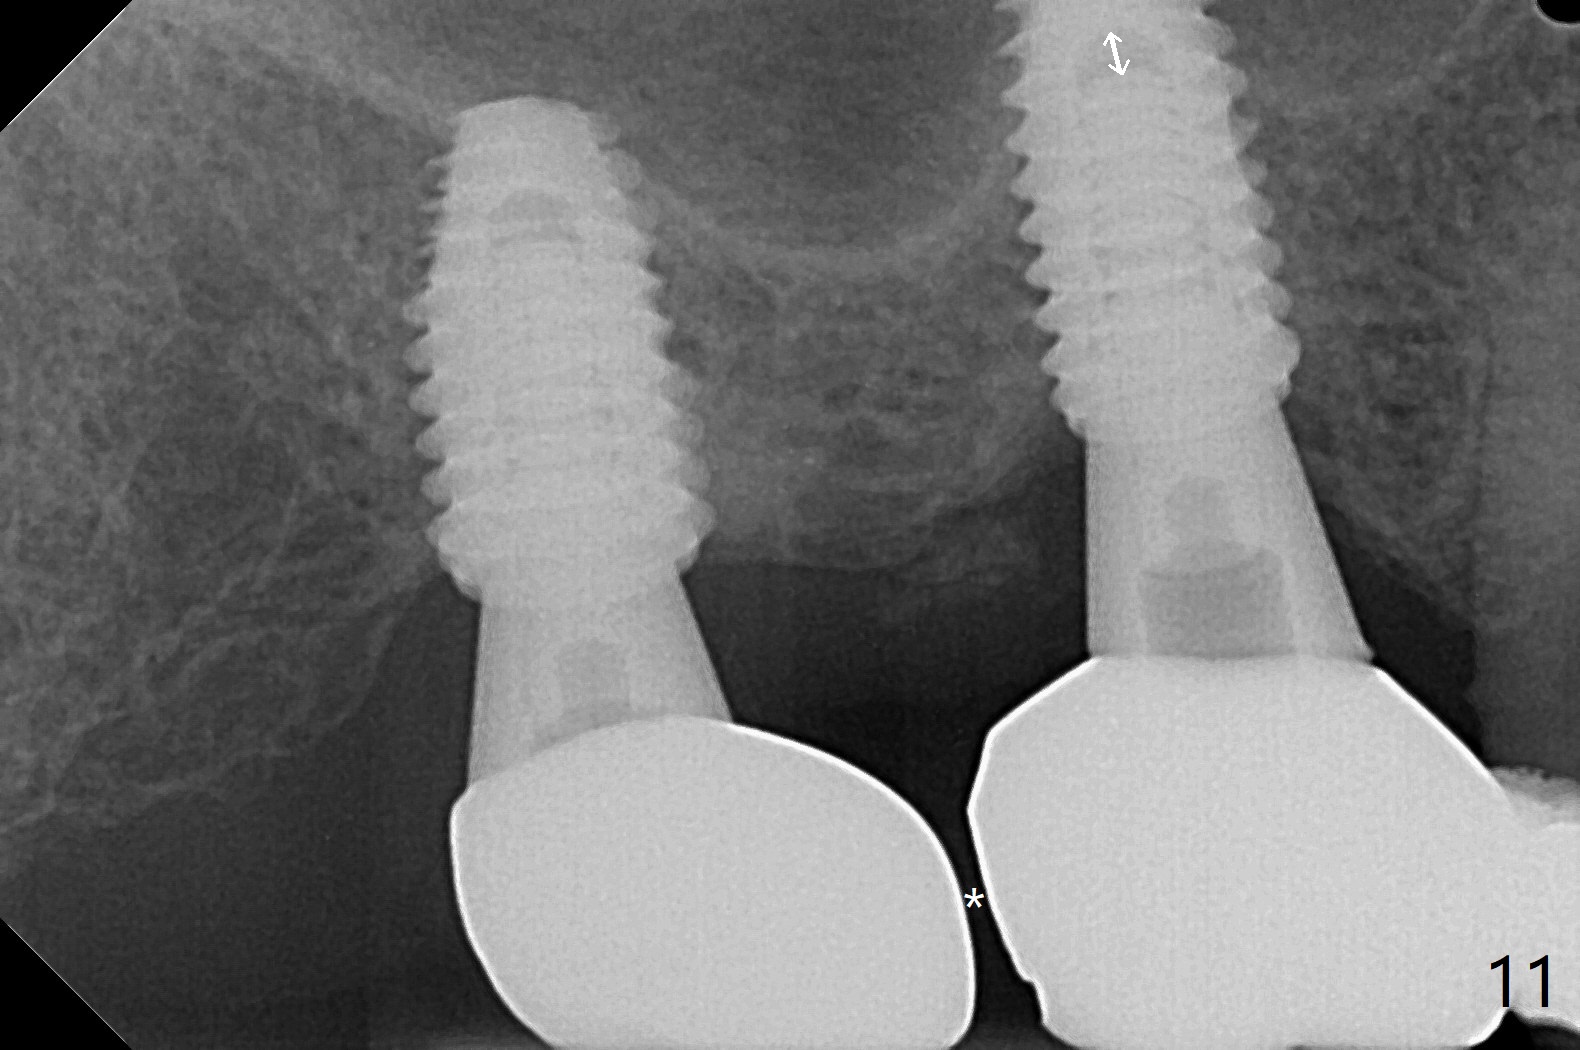

Osteotomy at the sites of #2 and 3 goes on as planned. Sinus lift using DIO 2.8 mm round bur with 6 and 7 mm stoppers (respectively) is carried on without certainty, because it is difficult to feel the stop through the osteotomy. The crest may be uneven or soft. It appears that the soft tissue landmark as a stop may be easier to identify. In fact a 3 mm IBS Magic Expander (an osteotome) was used for sinus lift at #3. The 2 implants are placed with 20 and 30 Ncm (Fig.1,2). Healing abutments are inserted. At 2-week follow-up, the patient reports "pain a few days earlier, took a pill of antibiotic, pain gone. UR metal is sharp". She does not take antibiotic regularly. Exam reveals that there is heavy plaque around #2,3 healing abutments. The buccal edge of #2 abutment is trimmed for comfort. Nearly 1 month postop, #3 healing abutment dislodges with buccal gingival erythema and edema with purulent discharge (Fig.3). Healing screw is placed at #3 with Amoxicillin and Chlorhexidine prescribed. One week later, the implant at #3 turns when the healing screw is retightened (Fig.4). After debridement, Vanilla graft is placed. There is no infection at #2 or 3 four months postop (Fig.5,6); the lingual gingiva is erythematous and edematous at #29 with mobility II (Fig.7 (vertical root fracture)). Uncover is conducted at the site of #3; there is no infection superficial 7.5 months postop (Fig.8). There is a large buccal defect upon incision with dark hemorrhage. In fact the bone density is low crestally (Fig.8 *). Bone graft is placed for the 2nd time. Eleven months later (1.5 years post implant placement), the bone regrows crestal (Fig.9 *). The crown at #3 is loose 1 year 5 months post cementation (Fig.10). After proximal trimming (Fig.11 *), the abutment at #3 is seated completely. After lab repair, crown oral cement, crown/abutment removal for excess cement removal, the crown/abutment cannot be torqued >25 Ncm (Fig.12, 30 Ncm). PA shows incomplete seating (Fig.12 <). Then the crown is sectioned so that the abutment has more freedom to be seated completely with pressure against the gingiva (the patient feels pain, Fig.13). Torque is 30 Ncm. After crown cementation, the abutment will not be removed for cement removal.